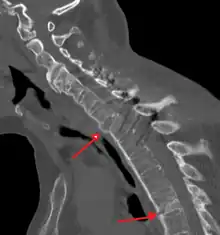

Imaging

X-rays

The earliest changes demonstrable by plain X-ray shows erosions and sclerosis in sacroiliac joints. Progression of the erosions leads to widening of the joint space and bony sclerosis. X-ray spine can reveal squaring of vertebrae with bony spur formation called syndesmophyte. This causes the bamboo spine appearance. A drawback of X-ray diagnosis is the signs and symptoms of AS have usually been established as long as 7–10 years prior to X-ray-evident changes occurring on a plain film X-ray, which means a delay of as long as 10 years before adequate therapies can be introduced.[26]

CT scan showing bamboo spine in ankylosing spondylitis